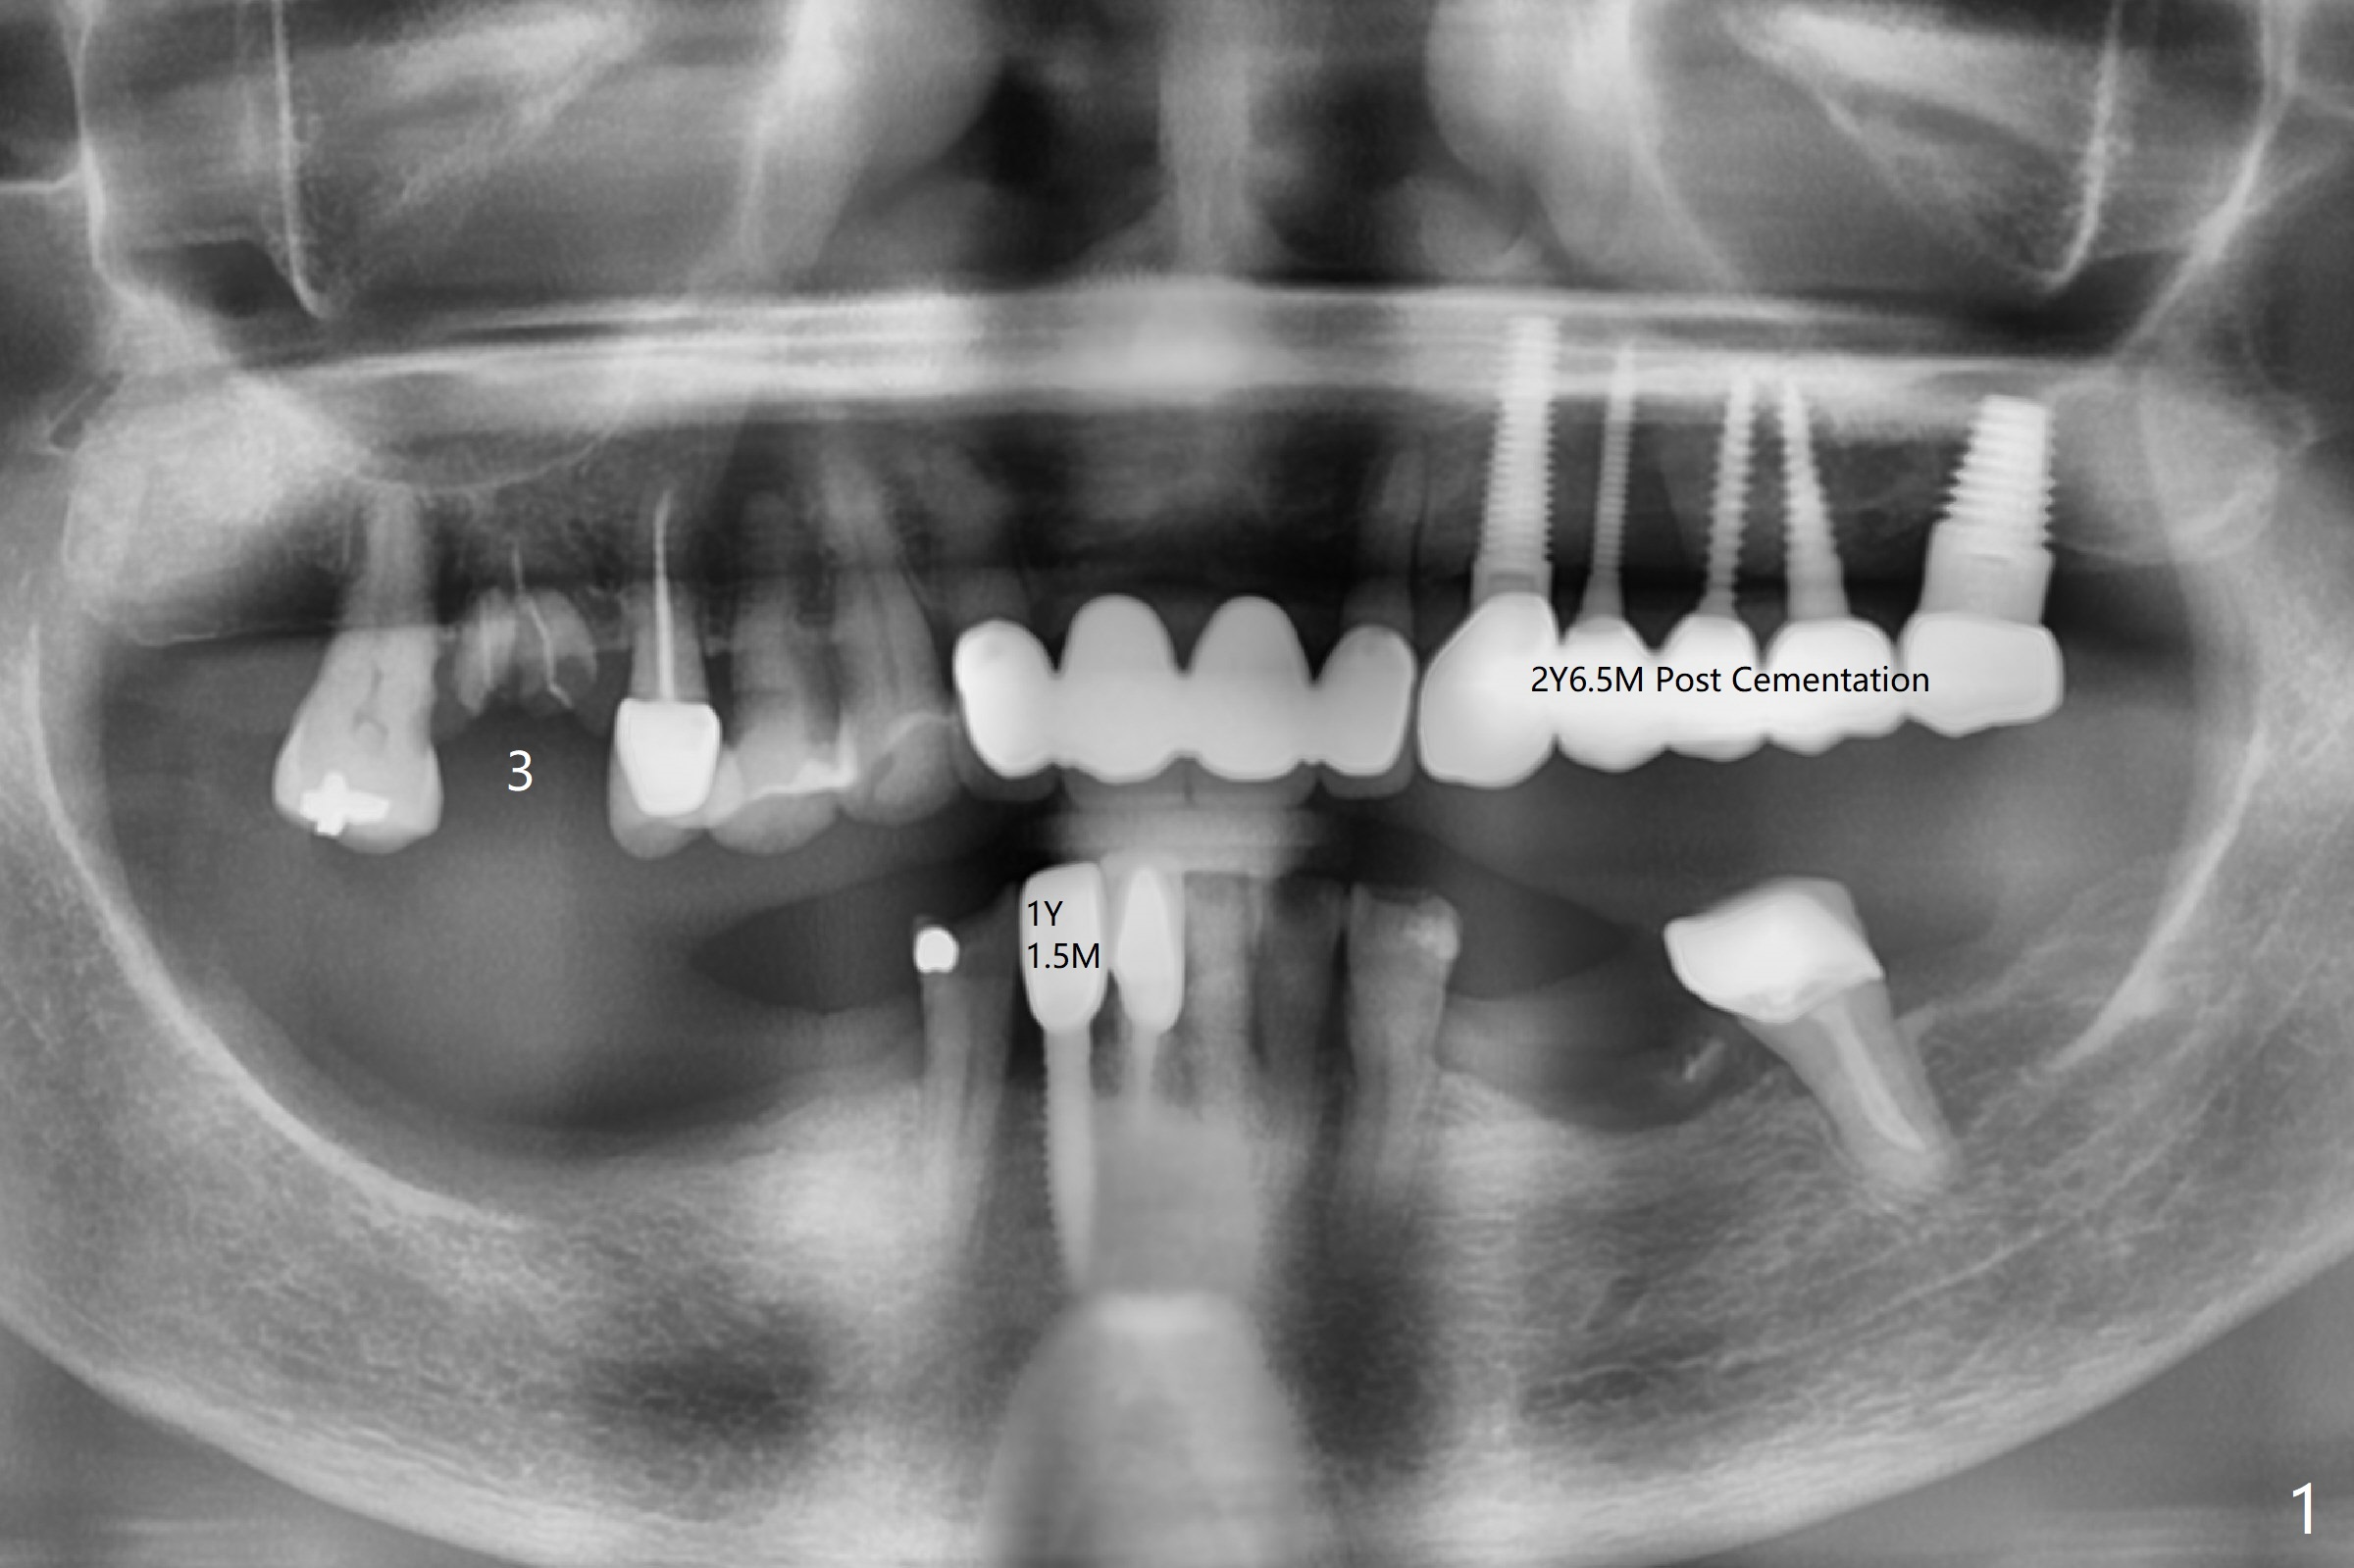

A 72-year-old woman returns with loss of crown at #3 one and 2 years post cementation at #26 and #11-15 (Fig.1). It appears that immediate implant achieves better trajectory with guide than without it when osteotomy involves the septal bone in a molar (Fig.2). Take photos after extraction, after initial osteotomy, and after implantation to show that the osteotomy stays in the middle of the socket in spite of the sloped septum.